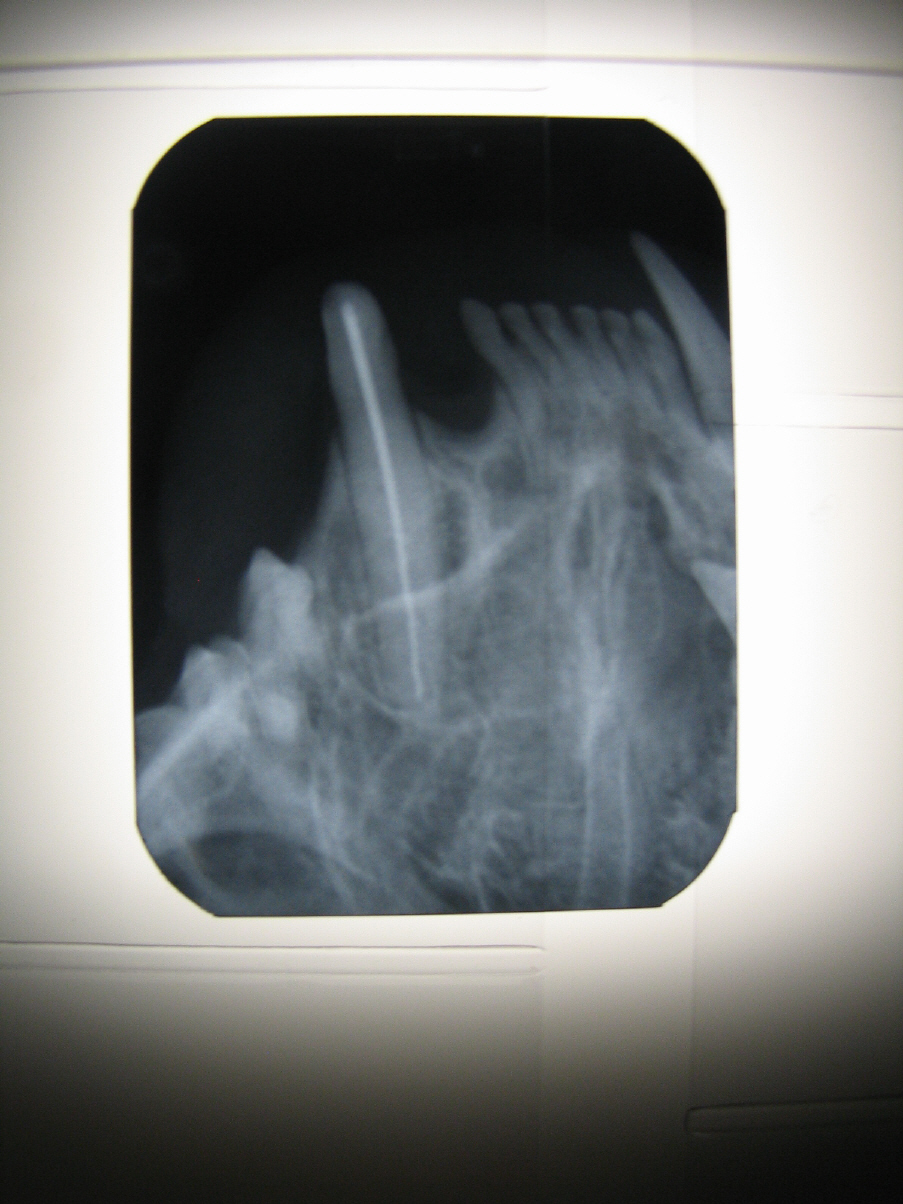

- Hochauflösendes digitales dentales Röntgen

- Zahnfüllungen und Wurzelkanalbehandlung (Endodontie)